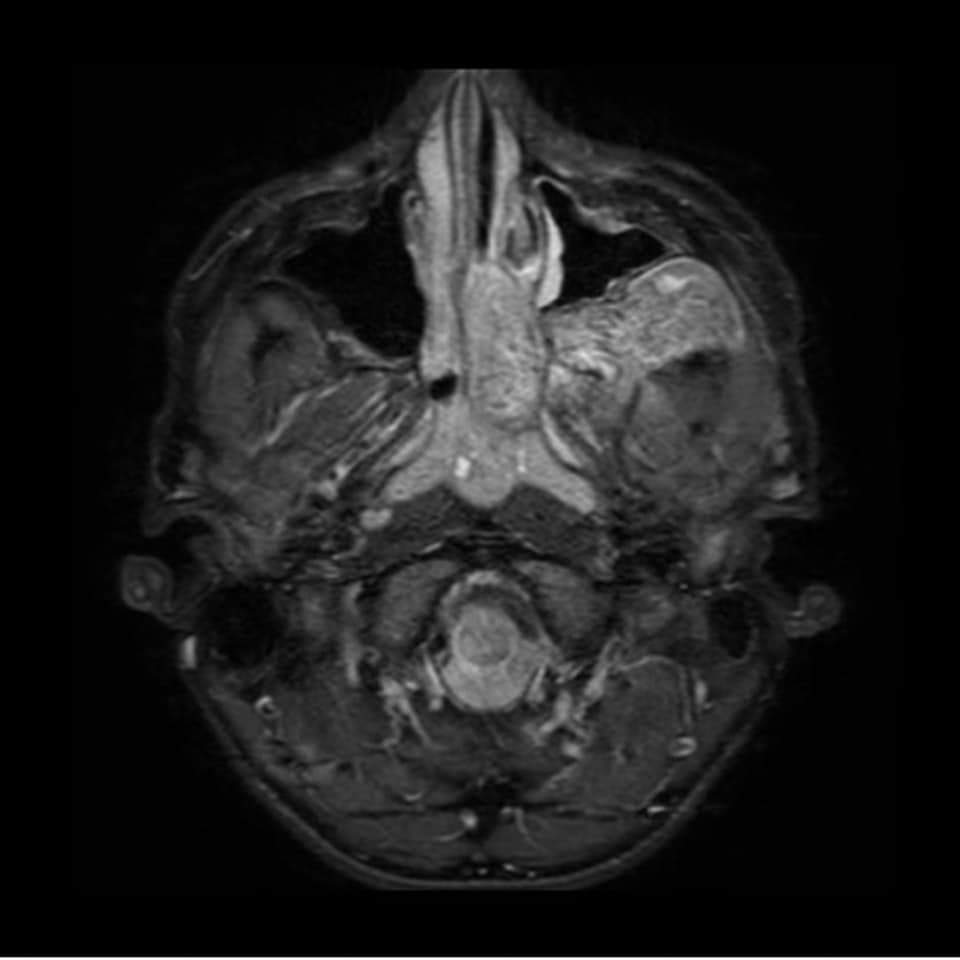

Tumor benigno (no canceroso) formado por vasos sanguíneos y tejido fibroso. Los angiofibromas nasofaríngeos juveniles aparecen en la parte posterior de la nariz y a veces se diseminan a la parte superior de la garganta, los senos paranasales y los huesos que rodean los ojos; en muy pocas ocasiones se diseminan al cerebro. Los signos y síntomas son secreción nasal, hemorragia nasal, dificultad para respirar por la nariz, sordera y tendencia a formar moretones. Los angiofibromas nasofaríngeos juveniles son más frecuentes en hombres jóvenes. Son un tipo de tumor vascular.

Imágenes de resonancia magnética.